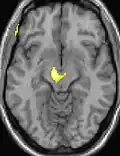

| Positron emission tomography (PET) shows brain areas being activated during pain. | ||

| Voxel-based morphometry shows brain area structural differences. | ||

Positron emission tomography (PET) scans indicate the brain areas which are activated during attack only, compared to pain free periods. These pictures show brain areas that are active during pain in yellow/orange color (called "pain matrix"). The area in the center (in all three views) is activated only during cluster headaches. The bottom row voxel-based morphometry shows structural brain differences between individuals with and without CH; only a portion of the hypothalamus is different.[37]